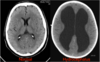

Diagnose? - Definition: "vand i hovedet". Udvidede hjerneventrikler på grund af øget mængde intraventrikulær cerebrospinalvæske (CSF)

Hydrocephalus

40

Hydrocephalus: Inddeling og Symptomer: * **Hos infantil/børn (ÅBNE suturer/fontaneller)**: øget hovedomfang, spændt fontanelle, nedsat øjenmotorik (solnedgangsblik), irritabilitet * **AKUT – Hos voksne (LUKKEDE suturer/fontaneller)**: hovedpine, kvalme/opkast, **bevidsthedspåvirkning (fald i GCS)**, papilødem * **Normaltrykshydrocephalus (NPH) – Hos ældre (> 60 år)**: triade: gangbesvær, demens, urininkontinens Behandling: * **Akut hydrocefalus**: ekstern ventrikeldrænage (EVD), behandle udløsende årsag (fx tumor, blødning, infektion) * **Kronisk hydrocefalus**: shunt (ventrikulo-peritoneal shunt) eller kirurgi (endoskopisk 3. ventrikulostomi)